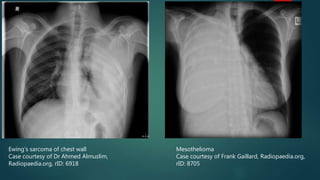

Chest wall or pleural mass

 If large enough, masses can cause hemithorax white-out

 Pleural mass – mesothelioma

 Chest wall mass – Ewing’s sarcoma

 Radiological findings:

 Vary by cause, can be nonspecific

 Can potentially displace adjacent structures

 Can cause rib destruction

Ewing’s sarcoma of chest wall

Case courtesy of Dr Ahmed Almuslim,

Radiopaedia.org, rID: 6918

Mesothelioma

Case courtesy of Frank Gaillard, Radiopaedia.org,

rID: 8705

Ewing’s sarcoma ofchest wall Case courtesy of Dr Ahmed Almuslim, Radiopaedia.org, rID: 6918 Mesothelioma Case courtesy of Frank Gaillard, Radiopaedia.org, rID: 8705